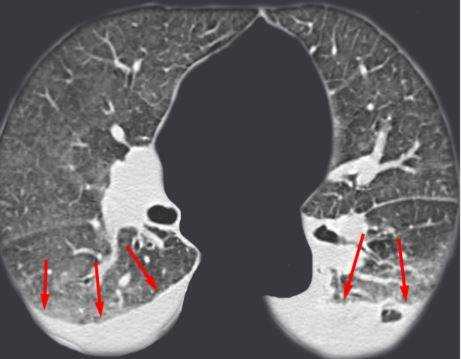

Выпот (красные стрелки) в обеих плевральных полостях.

Очаговые изменения на КТ легких, подозрительные на туберкулезное поражение (выделено красным)